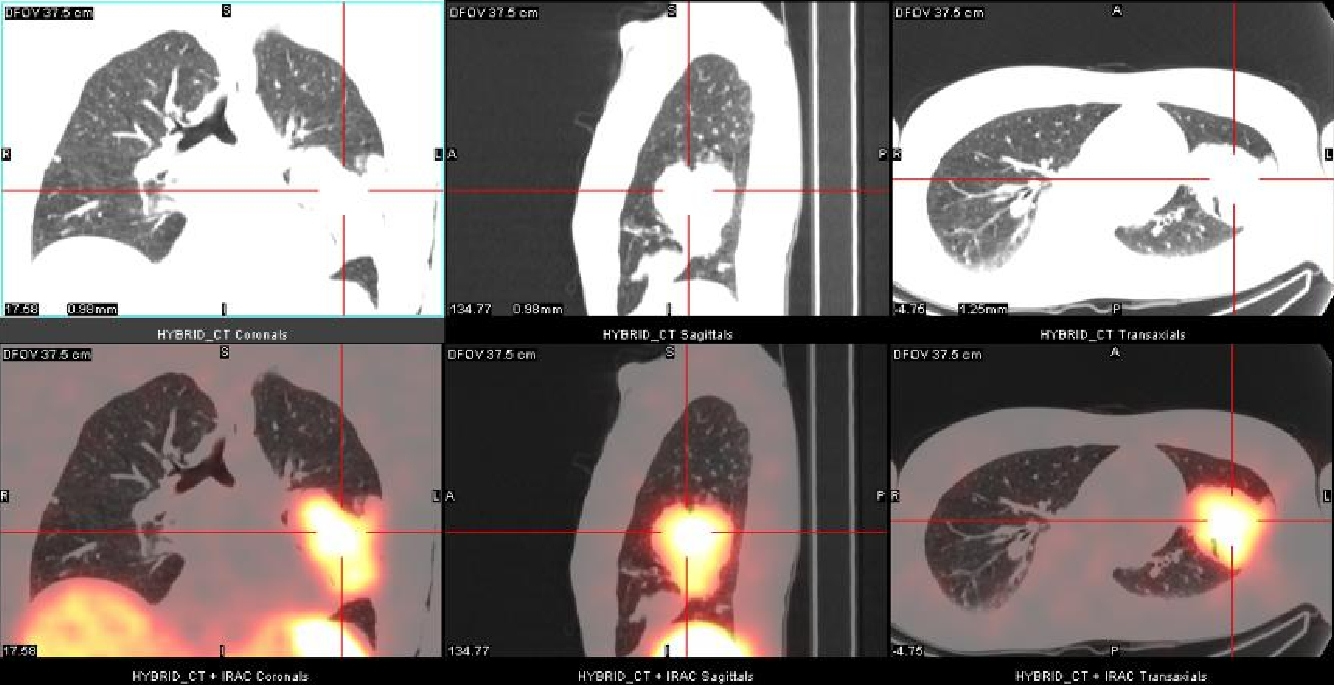

Uma quarta recorrência foi identificada por RM na região retro-orbital direita com progressão ipsilateral anterior para lobo temporal após cinco anos. Investigação pré-operatória constatou uma massa pulmonar na parte inferior do lobo superior esquerdo. Biópsia guiada por CT evidenciou meningioma atípico grau II. Um estudo com 111In-Oct SPECT/CT foi realizado como extensão diagnóstica. Foi evidenciada intensa fixação do 111In-Oct associada à presença de receptores de somatostatina a nível da lesão pulmonar (fig. 1), assim como na lesão temporal direita (fig. 2), confirmando recorrência. Tambén foi detectada fixação linfonodal direita (fig. 3).

Nosso paciente possuía uma lesão intracraniana extensa (47x30x27mm) com metástase pulmonar assintomática. A massa pulmonar foi descoberta incidentalmente durante investigação pré-operatória; uma biópsia pulmonar guiada por CT revelou meningioma atípico. 111In-Oct SPECT/CT caracterizou a massa pulmonar, confirmando, ainda, recorrência local e envolvimento linfonodal.